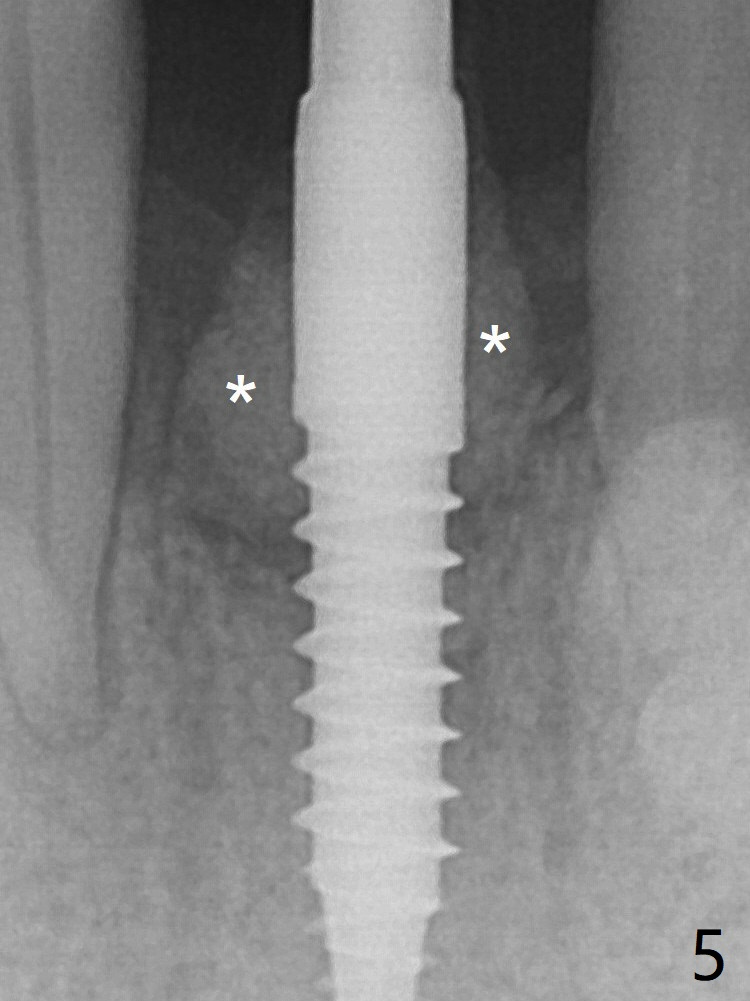

Since the gingiva is as thick as 7.5 mm (Fig.3 arrow), a 3x14 mm 1-piece implant with 4 mm cuff is placed (Fig.5); three implant threads are outside the native bone; with allograft (*) placed and the neighboring crests being coronal to the threads, the chance of periimplantitis should be remote. An immediate provisional is fabricated to contain the graft in place. The top 3 threads appear to be contacted by the newly formed crestal bone 6 months postop (Fig.6 *). Bone appears to have grown into the space between implant threads 6 months post cementation (13 months postop).